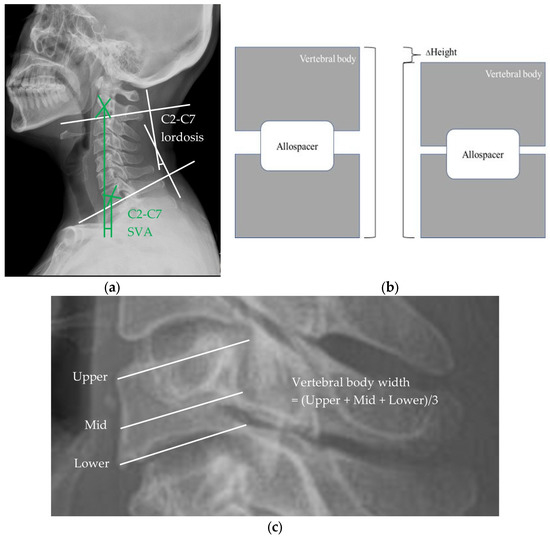

2.3. Evaluation of Radiological Outcomes

3.2. Cervical Spine Sagittal Balance

3.3. Subsidence

3.4. Vertebral Body Width